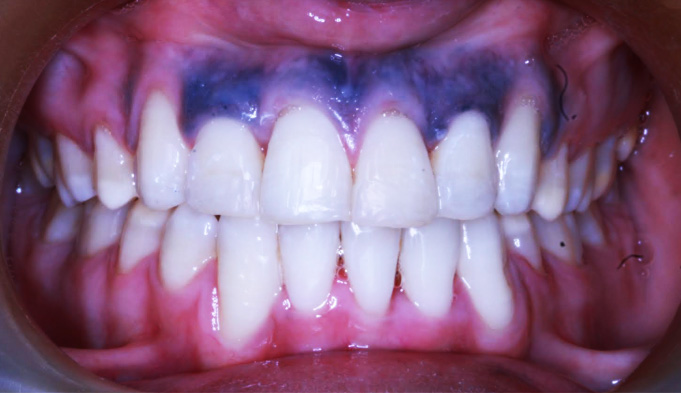

After-treatment images

After completion of orthodontic treatment, the patient showed:

• Properly aligned teeth

• Improved mouth closure

• A natural smile arc with improved esthetics, appearing even better than veneers